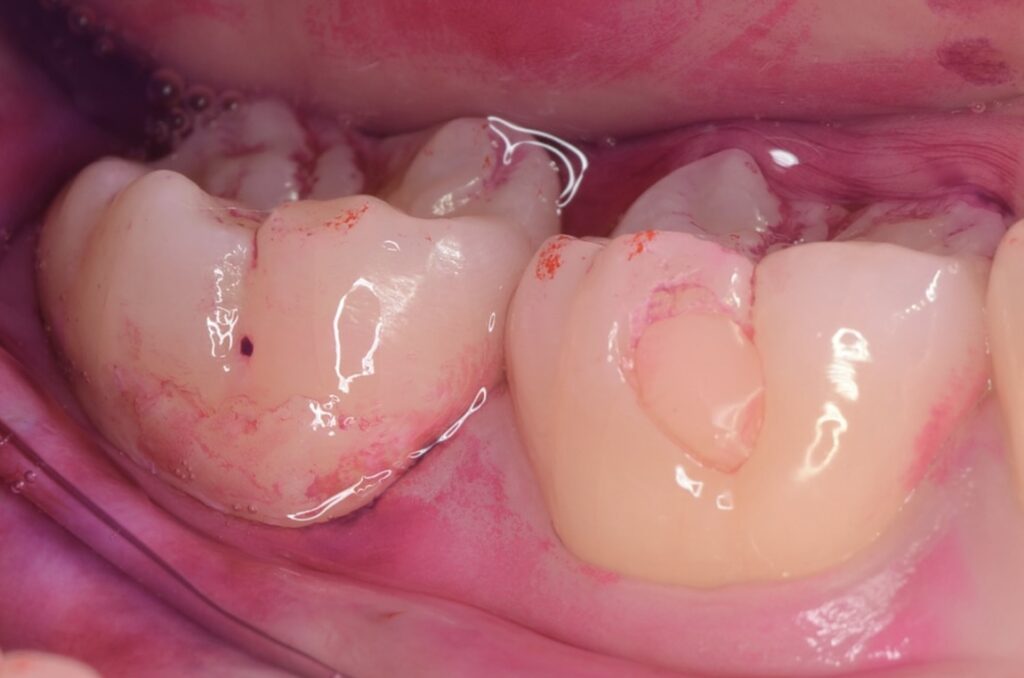

20代 虫歯治療 VPT(歯髄温存療法)ダイレクトボンディング #54

Before

After

| 年齢 | 20代 | 治療方法 | VPT(歯髄温存療法)/ダイレクトボンディング |

| 性別 | 女性 | 通院回数 | 3回 |

| 主訴 | むし歯を治したい /神経を取りたくない | 費用 | 286,000円(税込) |

| 治療のメリット | 神経を保存できる。歯を削る量を少なくできる。自然な形にできる | ||

| 治療のデメリット | 大きい虫歯治療には適応できない場合がある | ||